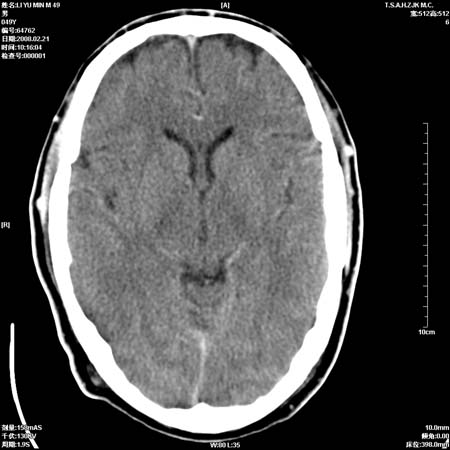

男性, 49岁, 头痛, 行ct检查后, 我科一名大夫报了蛛网膜下腔出血, 请大家讨论!

大脑纵裂池及鞍上池应该有蛛血

支持蛛网膜下腔出血。